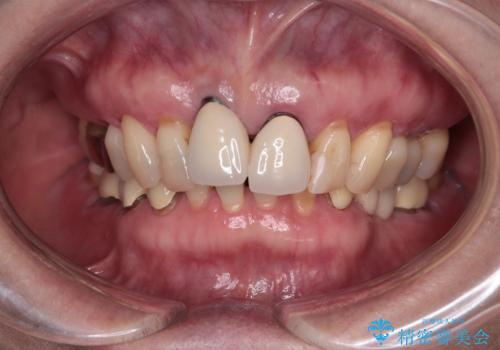

【海外から通院】統一感のない前歯をきれいに オールセラミッククラウン治療

- 歯肉ラインの段差や、歯根が黒く見えている前歯を気にして来院された患者様です。

海外に在住で、年に2度ほど帰国するタイミングで治療を行いたいとのことでした。

前歯のインプラントは埋入されたポジションが望ましい位置ではなく、インプラントを活用して段差を回収することは不可能と判断し、歯肉移植によりインプラントを隠して、ブリッジにて歯肉ラインを整えることとしました。

臼歯部の治療も必要と判断されましたが、前歯部を中心とした審美領域をオールセラミッククラウンによる補綴治療を行うこととしました。

帰国時のみの治療であったため、治療期間は長くなりましたが、最小限の来院回数で、気になっていた前歯をきれいに整えることができました。